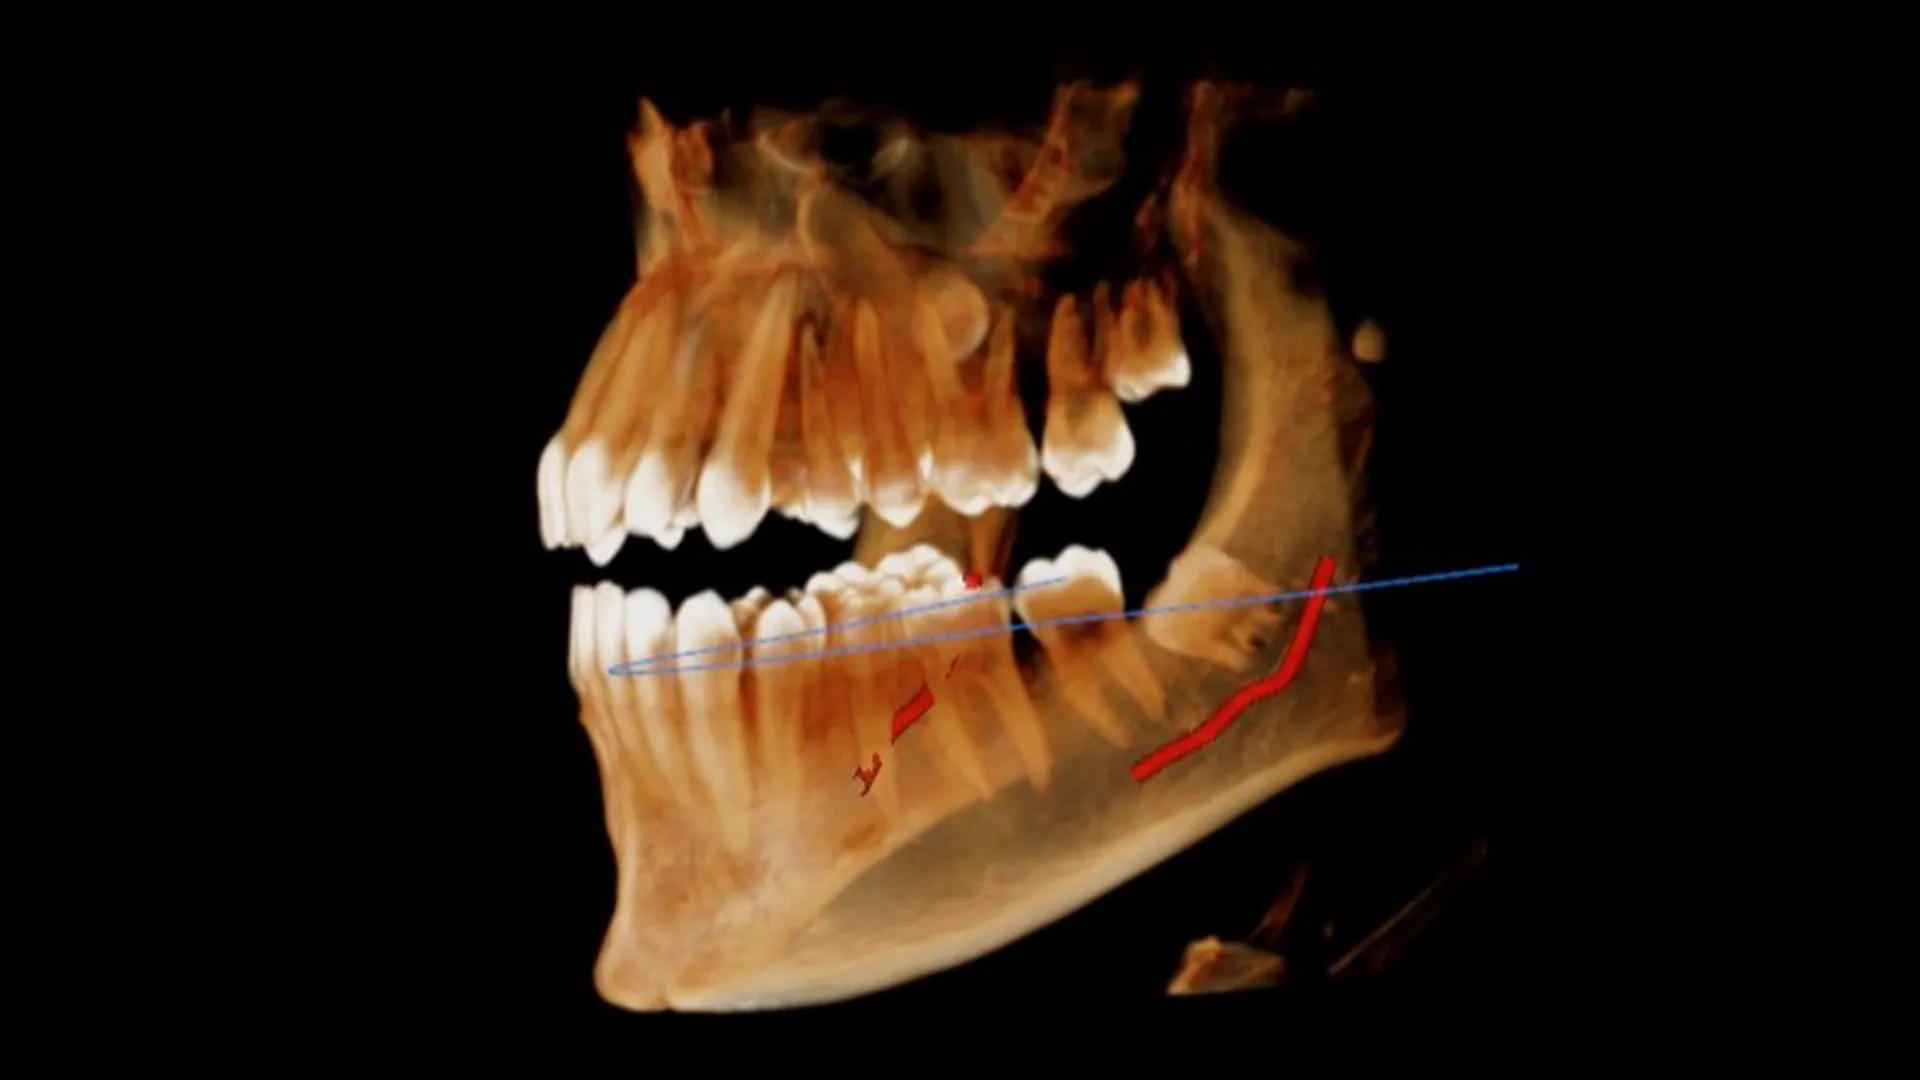

Le CBCT (Cone Beam Computed Tomography), ou scanner 3D à faisceau conique, est un appareil d'imagerie médicale de dernière génération. Contrairement à la radiographie panoramique qui produit une image 2D aplatie, le CBCT acquiert directement un volume de données, permettant la reconstruction d'images en trois dimensions sous tous les angles.

Le CBCT : Acquiert directement un volume complet en une seule rotation. À partir de ce bloc de données unique, l'ordinateur peut recalculer des coupes virtuelles dans n'importe quel plan (axial, sagittal, coronal) et avec n'importe quelle épaisseur, sans perte d'information.

La différence fondamentale est que le CBCT capture un "bloc" d'informations 3D d'un seul coup. À partir de ce bloc, le praticien peut virtuellement "saucissonner" l'image dans tous les sens pour l'analyser sous tous les angles.

Le CBCT offre une bien meilleure résolution pour l'imagerie osseuse que le scanner médical conventionnel, grâce à une taille de voxel (le plus petit élément d'un volume 3D, comme un pixel en 3D) beaucoup plus petite. Cela permet de visualiser des détails anatomiques extrêmement fins.

Évitement des obstacles anatomiques : Localisation exacte du nerf alvéolaire inférieur, des sinus maxillaires et des vaisseaux sanguins pour minimiser les risques per-opératoires.

Extractions complexes : Évaluation de la relation des dents de sagesse avec le nerf ou des racines avec le sinus.

Sécurité accrue et réduction des risques chirurgicaux : En offrant une "carte 3D" précise de la région à opérer, le CBCT permet au praticien d'anticiper les difficultés et d'éviter les complications telles que les lésions nerveuses, les perforations sinusales ou la pose d'implants dans une position non optimale.